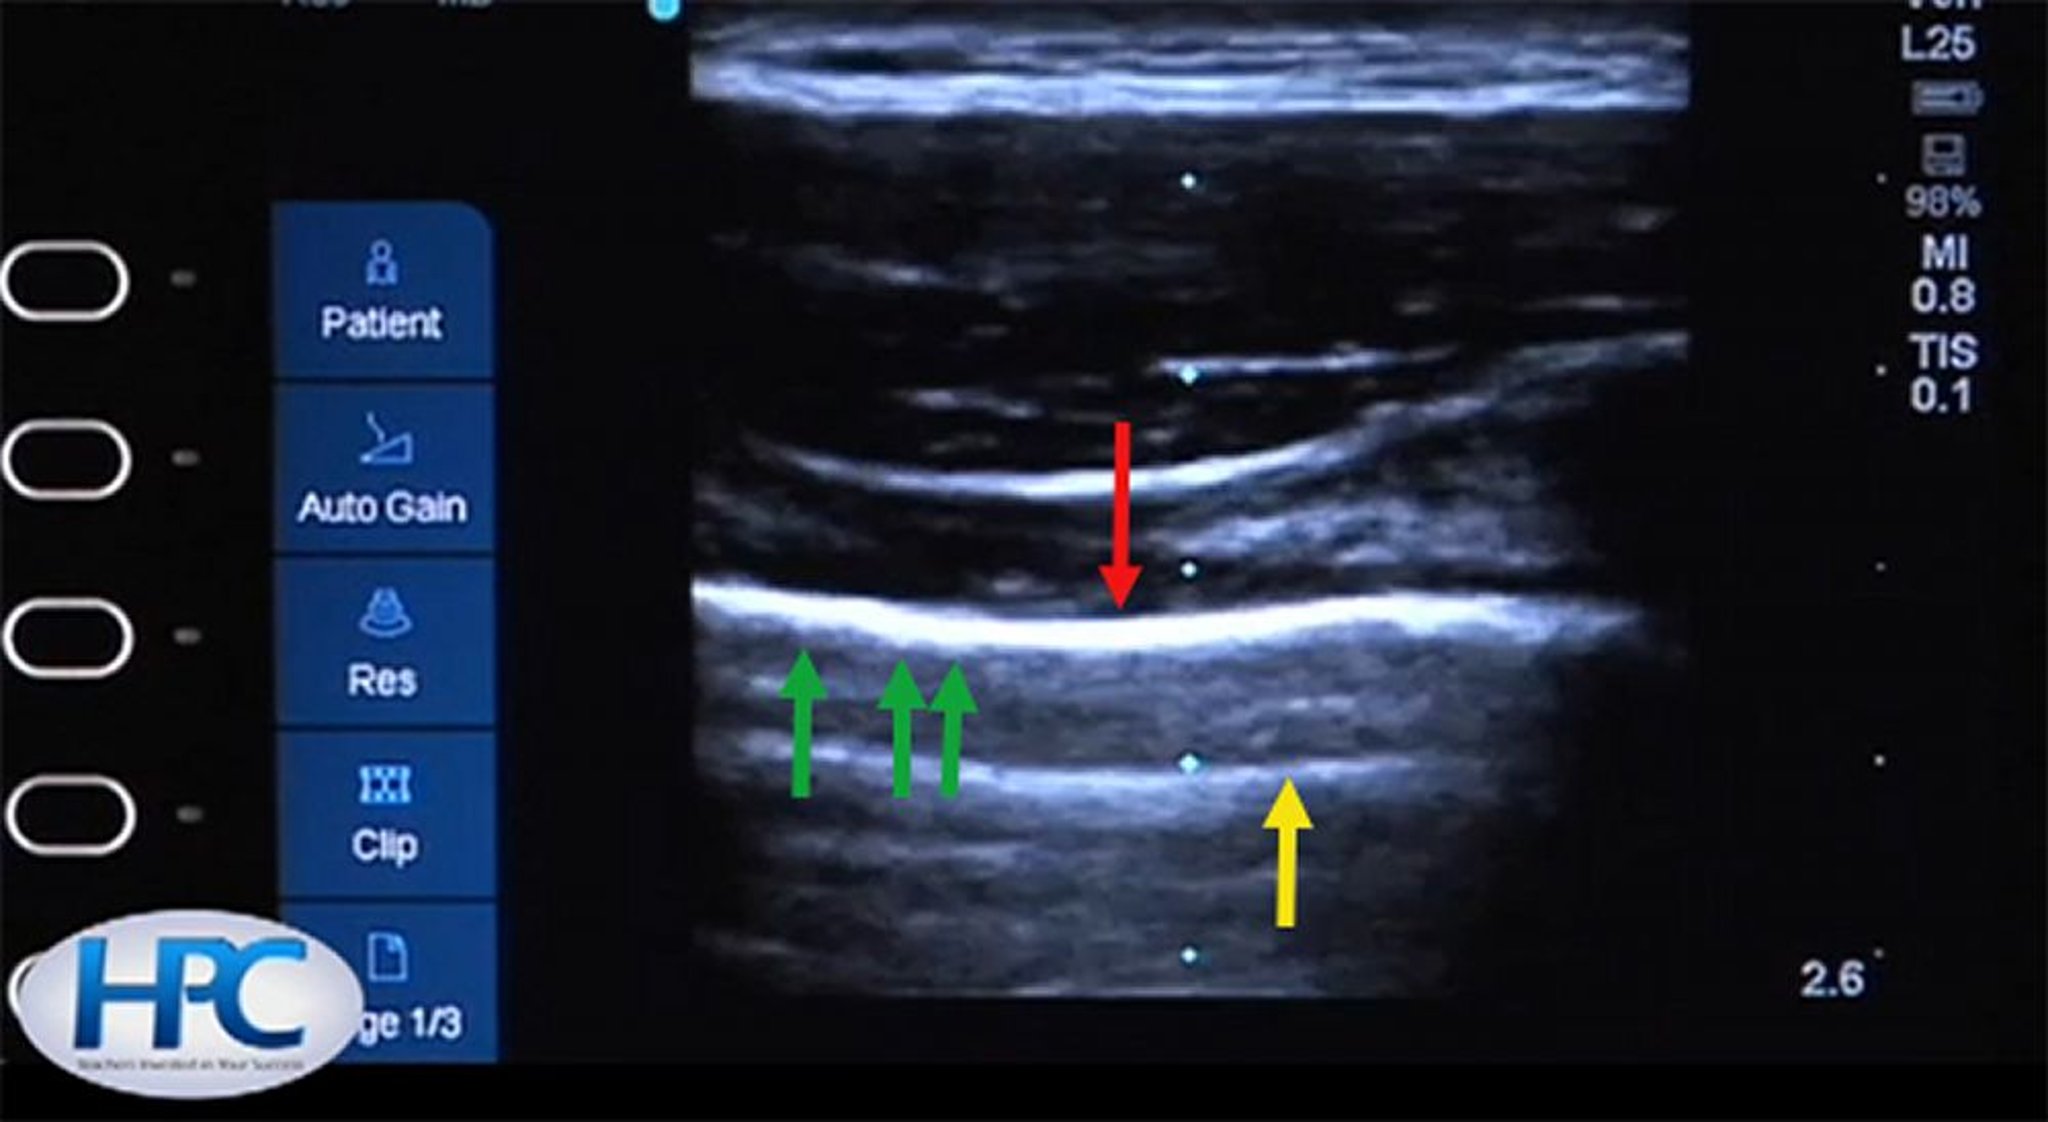

Ligne pleurale normale

La ligne pleurale est hyperéchogène (flèche rouge). Pendant la respiration, le glissement des côtes fait scintiller la ligne pleurale et crée une apparence de "ants on a log (tartine au beurre de cacahuète saupoudré de chocolat)" sur une vidéo en temps réel (flèches vertes). Des lignes A (flèche jaune) apparaissent du fait de la réflexion artificielle des ondes ultrasonores.